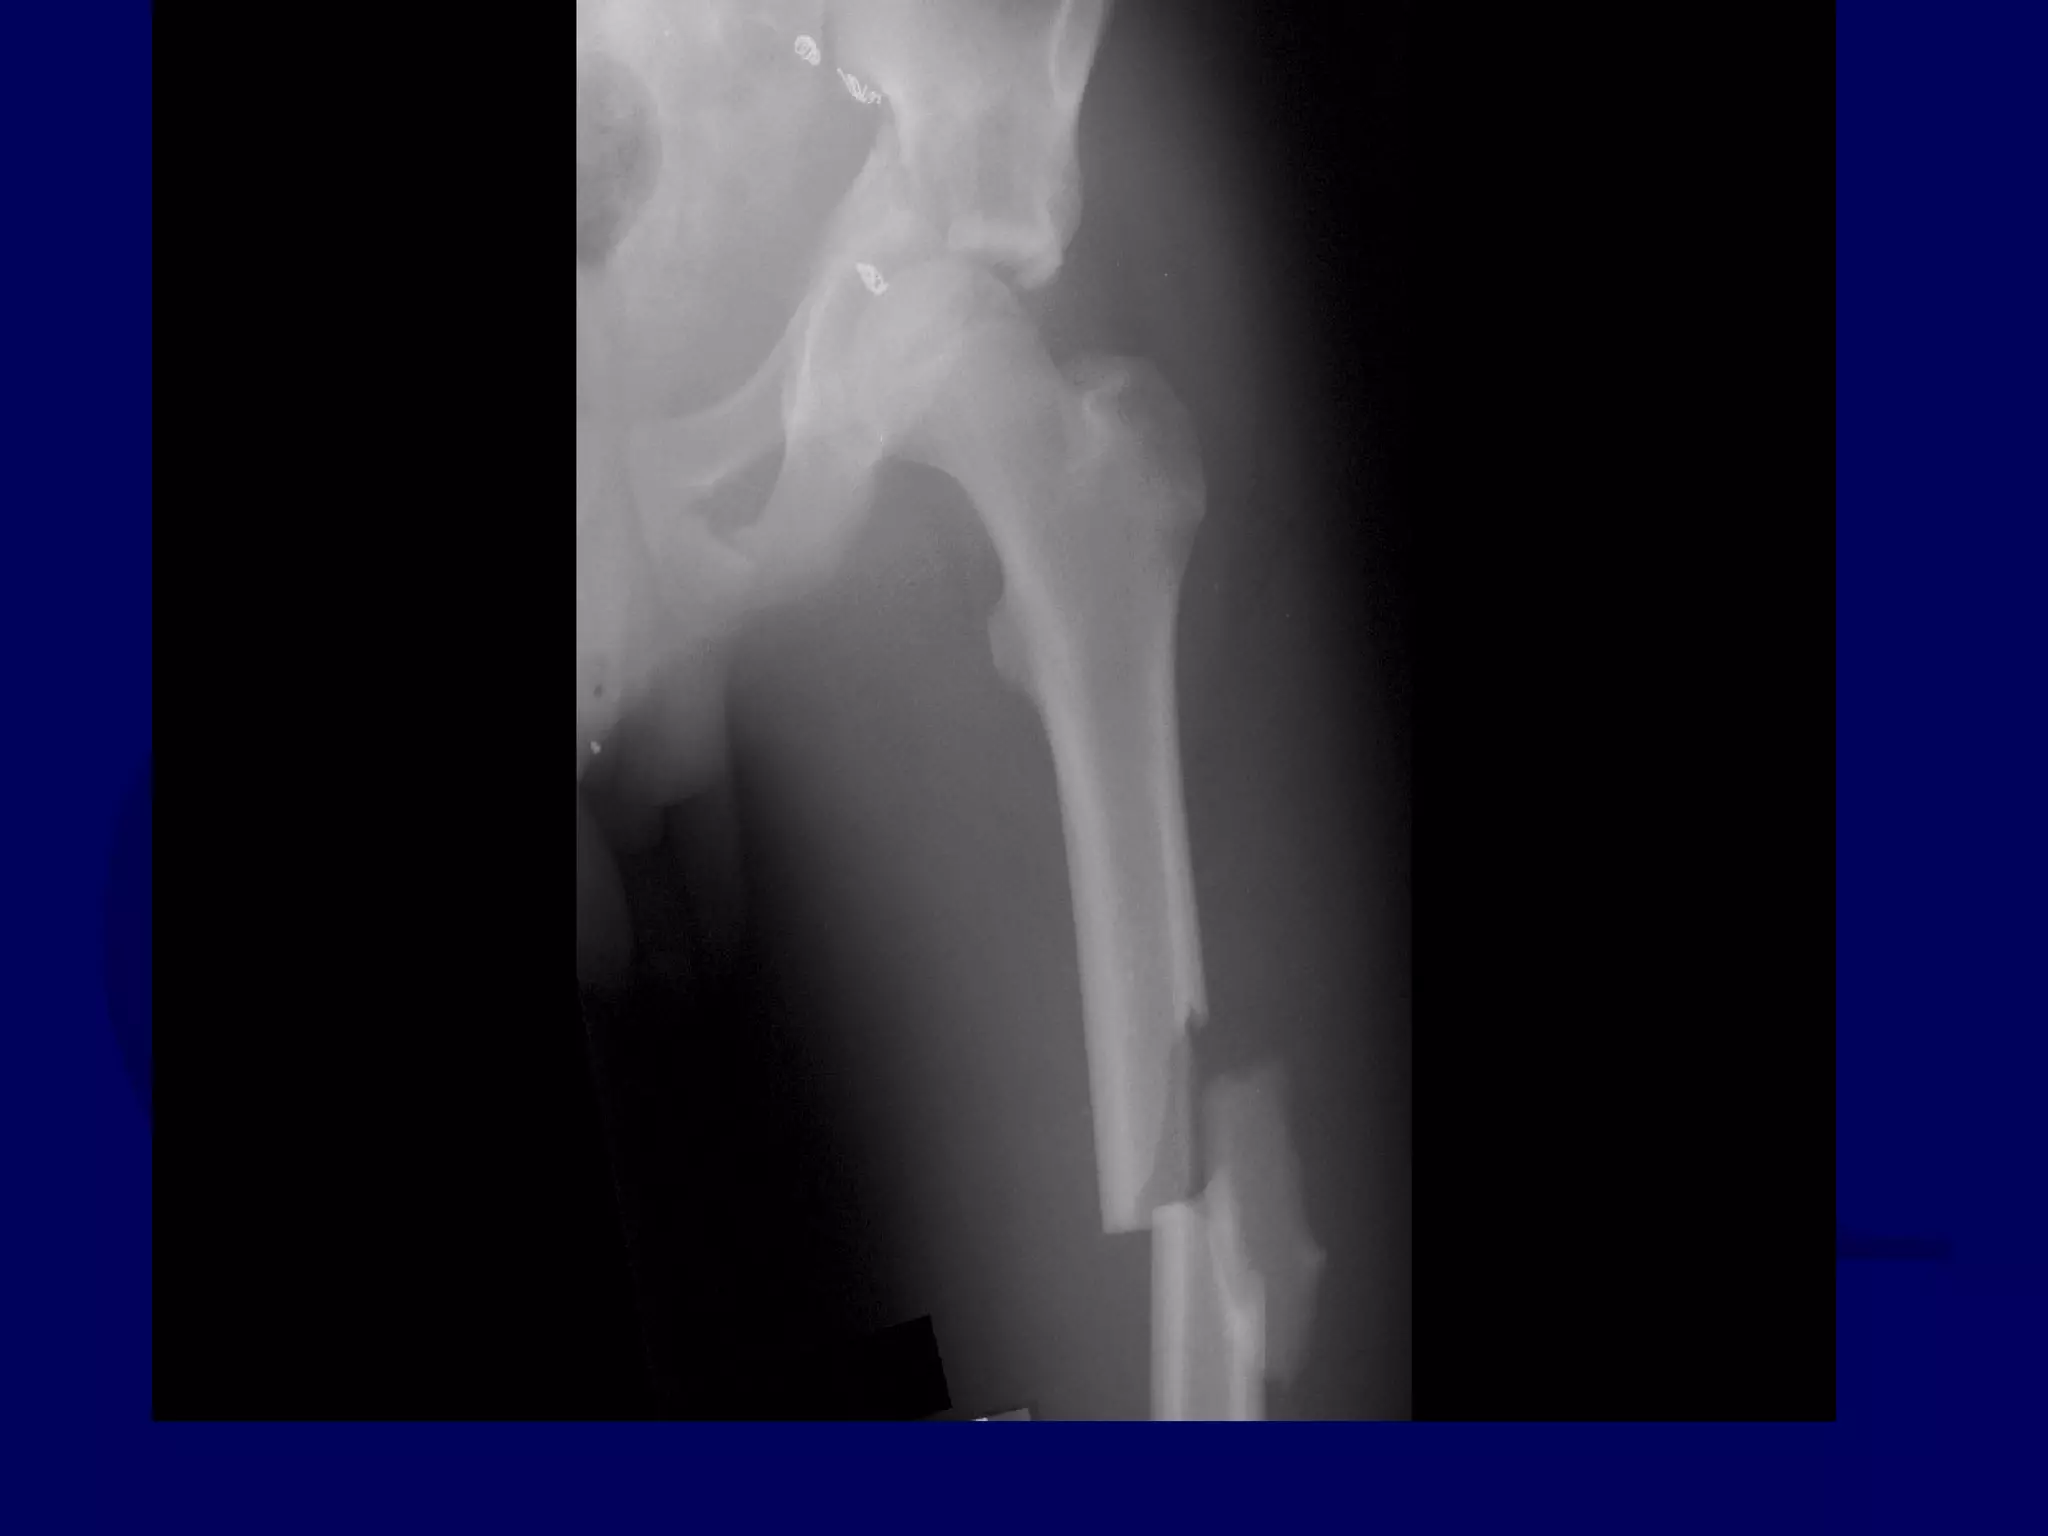

Special Case

“T-Type” Acetabular Fracture

Proximal Femur Fracture

14 y.o. Male

Sequential K-L / Ilioinguinal

Approaches

P.J. 00.12.16